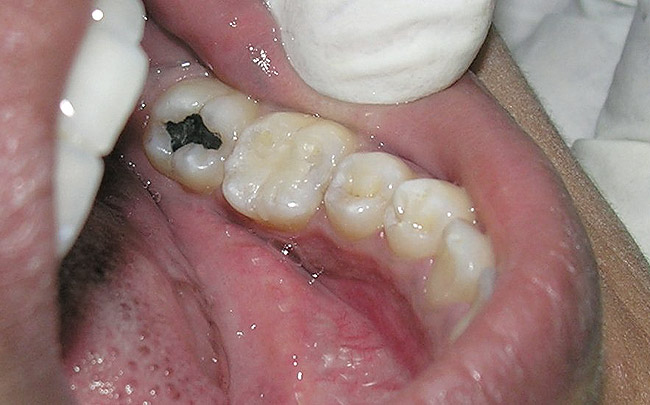

Figure 5  Clinical applications of RBCs for posterior restorations: occlusal caries restored with silorane-based RBC

Figure 5

Figure 6  Clinical applications of RBCs for posterior restorations: occlusal caries restored with silorane-based RBC

Figure 6

The search for an ideal direct esthetic restorative material is still ongoing. Among the array of RBC materials, some are readily available in the market (flowable, packable, and fiber-reinforced), others have just recently been introduced (siloranes-based), and a few are still in development phase (fluoride-releasing). Individual properties of different RBC materials define their advantages, disadvantages, and clinical uses. Each type of RBC material has its own virtues in some clinical aspects and shortcomings in other aspects. Every material possesses either one or the other ideal properties of a restorative material, but not all of them. Therefore, it is important for a clinician to use every material judiciously and for a clinical application for which it is best suited (Figure 5, Figure 6, Figure 7, Figure 8, Figure 9 and Figure 10).